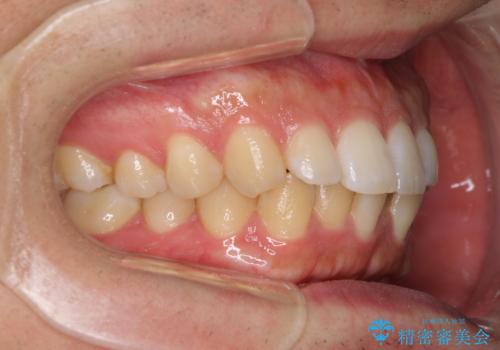

前歯のデコボコと突出感 インビザラインにて矯正治療

インビザラインによる上下歯列の側方拡大と後方移動、IPR(歯と歯の間を削る)にるスペースの獲得により歯列を整えることとしました。

左上の小臼歯は捻転が強く、あえて180逆向きの状態で終了させる治療計画としました。

ご自宅と職場がともに遠方であったため、治療期間は長くなりましたが、患者様も我々も期待して以上に口元の突出感を改善することができました。